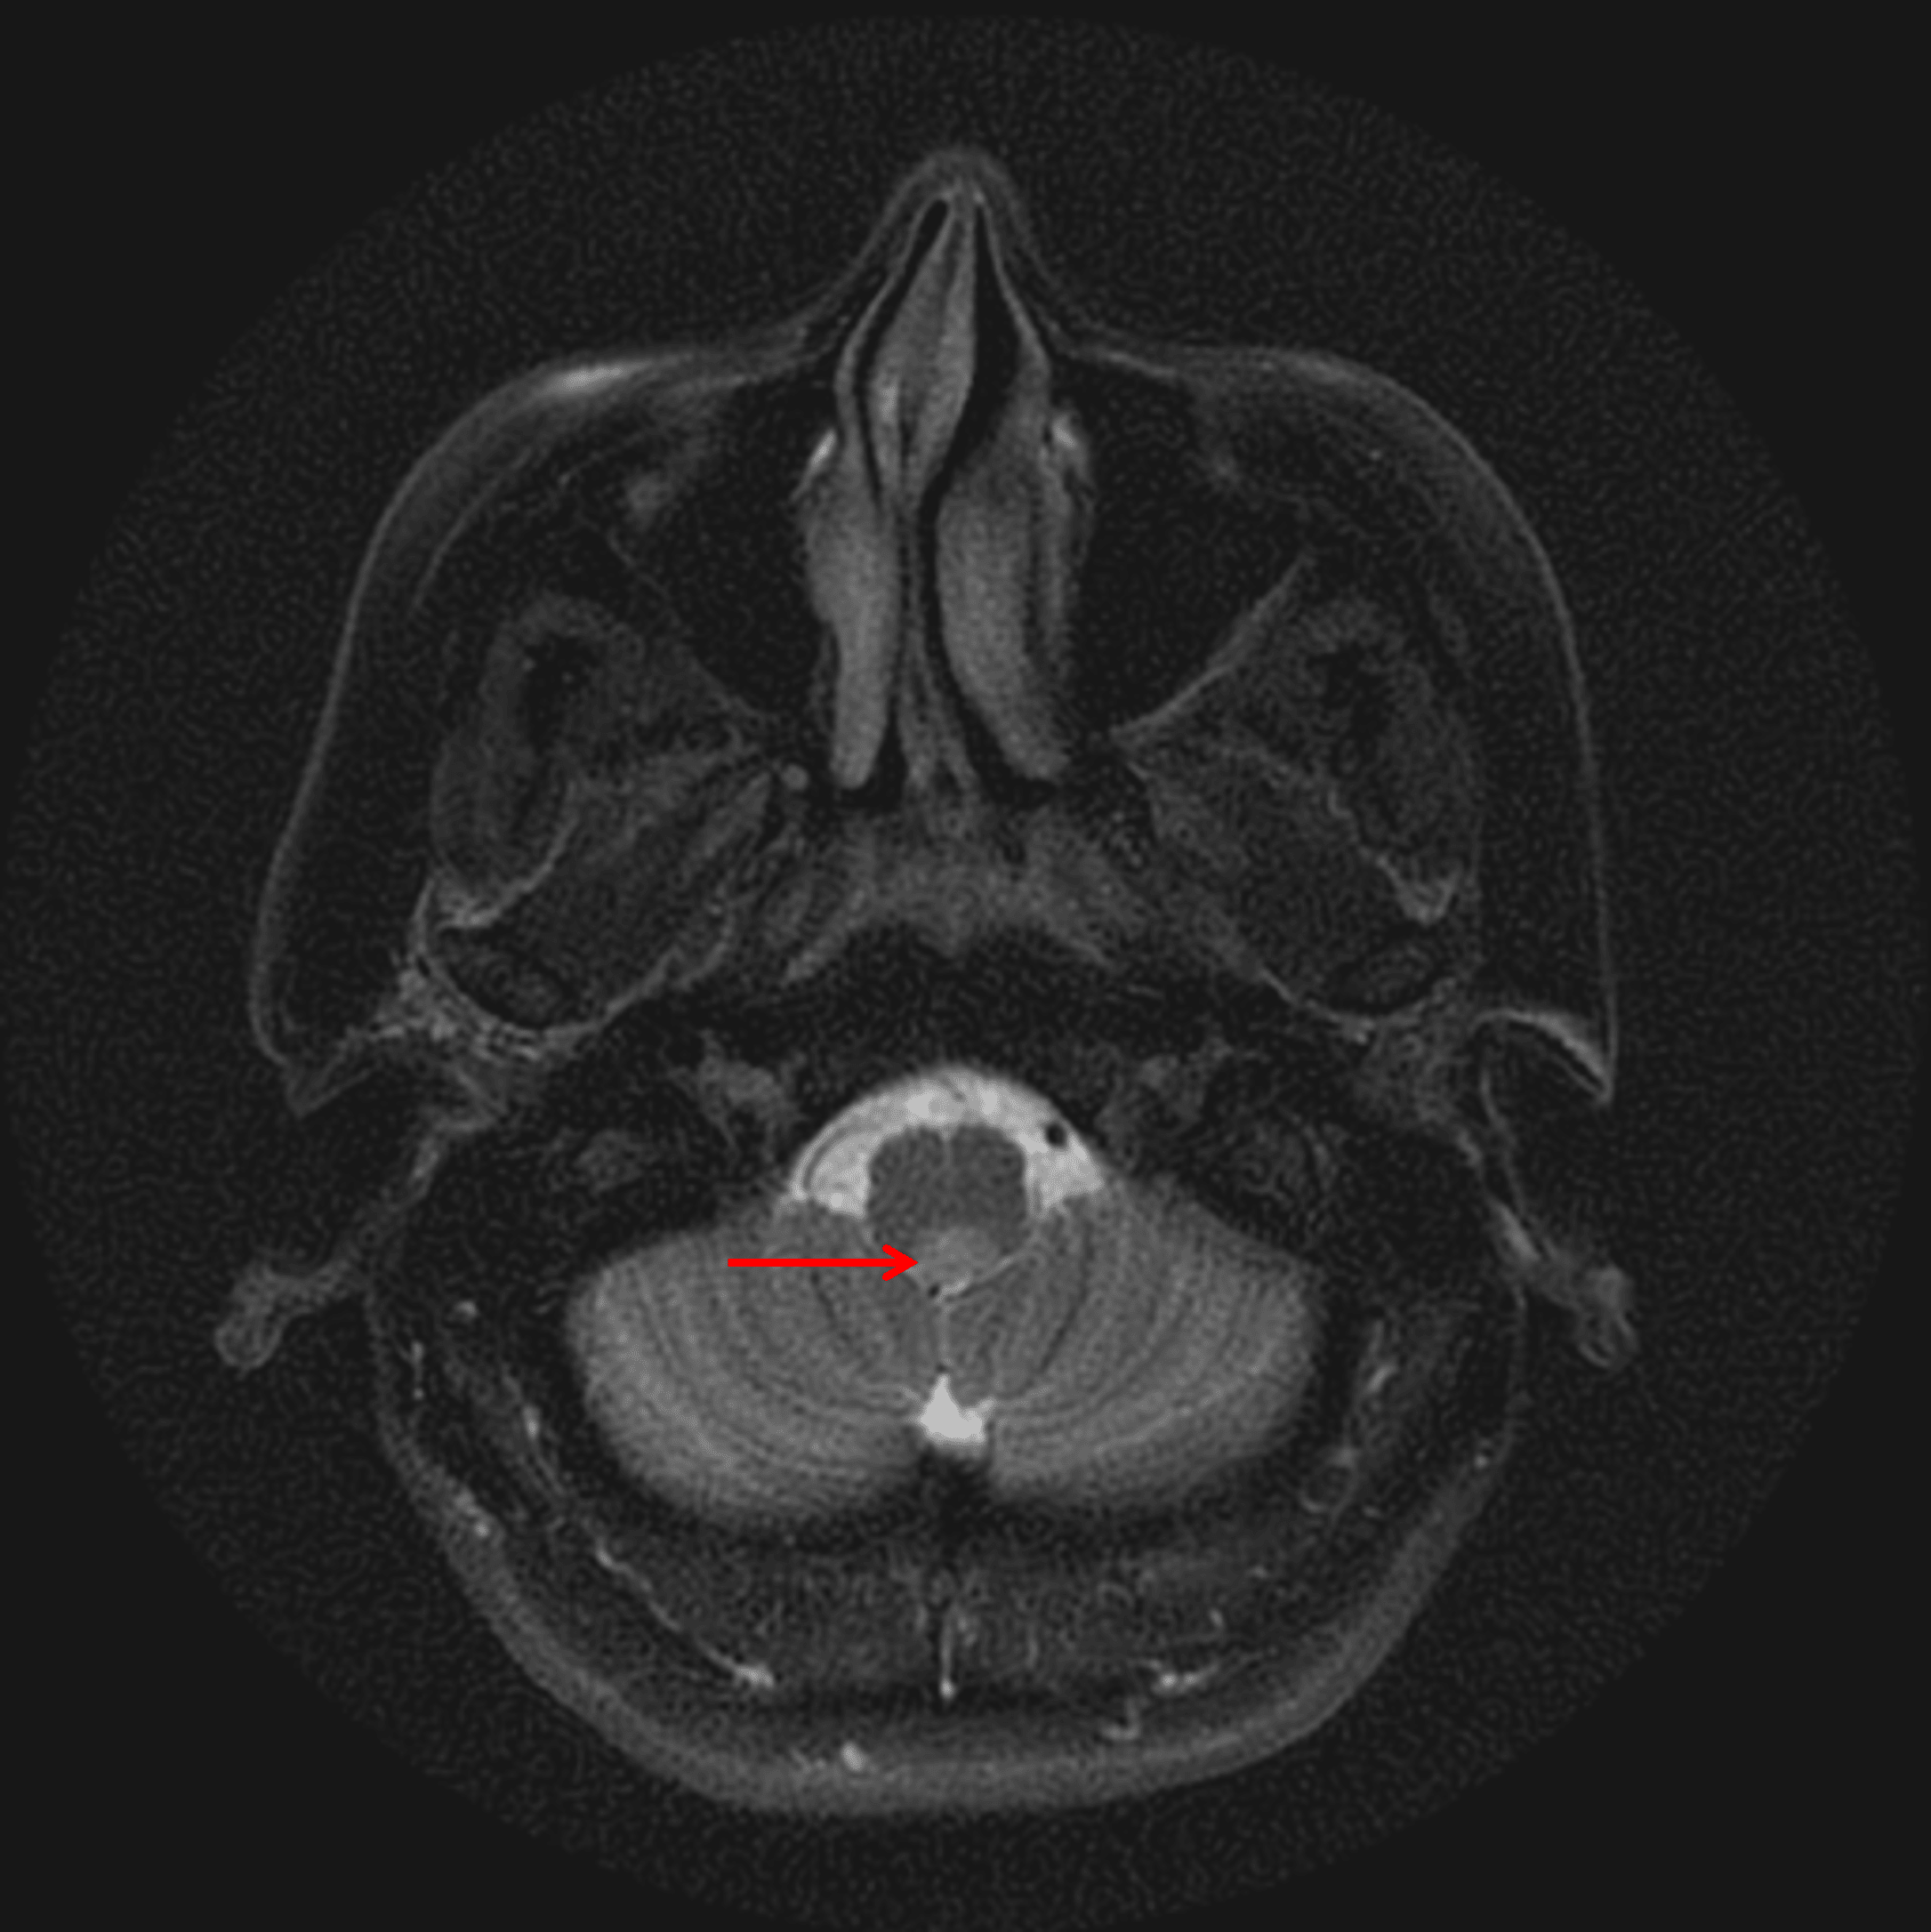

Mild corresponding T2 signal hyperintensity (red arrow).